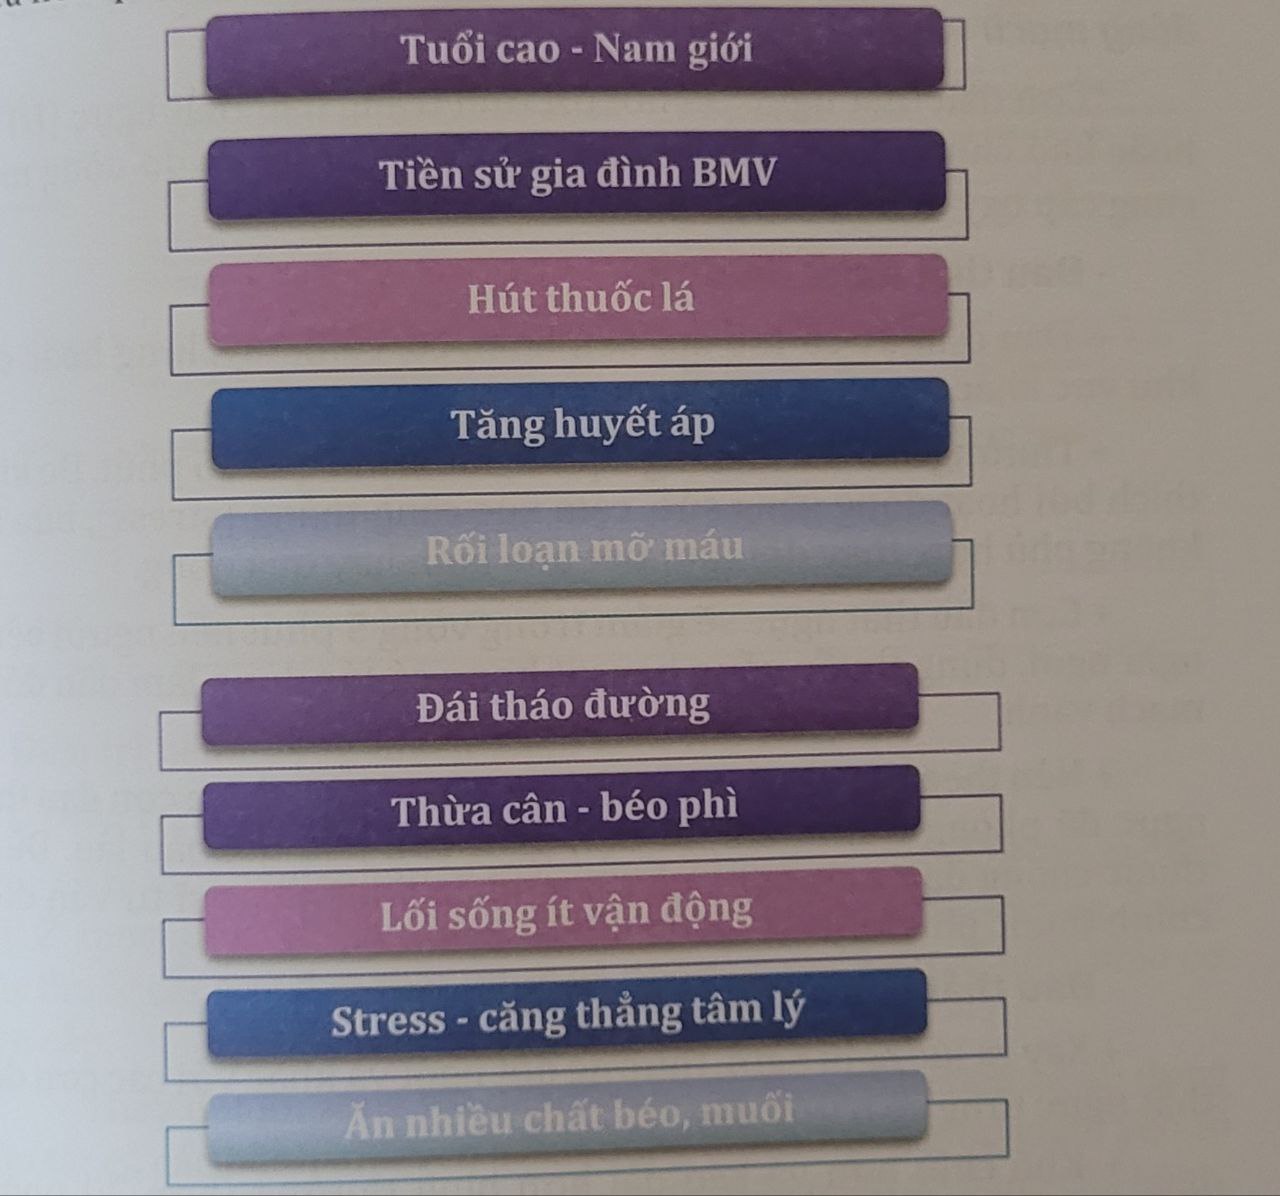

3. Các yếu tố nguy cơ của bệnh mạch vành (BMV)

Các yếu tố nguy cơ bệnh động mạch vành

Các yếu tố nguy cơ bệnh động mạch vành

– Tuổi càng cao càng làm tăng nguy cơ bị tổn thương và hẹp động mạch vành.

– Nam giới có nguy cơ mắc bệnh mạch vành cao hơn nữ. Với phụ nữ sau mãn kinh nguy cơ sẽ tăng lên.

– Tiền sử gia đình (yếu tố di truyền): trong gia đình có ông bà, cha mẹ bị bệnh động mạch vành cũng góp phần gia tăng tỷ lệ mắc bệnh cho những người con.

– Huyết áp cao không được kiểm soát tốt có thể dẫn đến động mạch vành bị xơ cứng và dày lên, dẫn tới hẹp động mạch vành.

– Rối loạn mỡ máu: mức cholesterol trong máu cao làm tăng mức xơ vữa. Trong đó, phân tử LDL cholesterol “xấu” cao, HDL cholesterol “tốt” thấp, góp phần vào sự phát triển xơ vữa động mạch vành.

– Đái tháo đường và tình trạng tăng đường huyết tăng nguy cơ xơ vữa các động mạch toàn cơ thể (trong đó có cả động mạch vành).

– Các yếu tố phổ biến khác: hút thuốc lá, béo phì – thừa cân, lối sống ít vận động, stress – lo âu hay chế độ ăn uống kém lành mạnh như ăn quá nhiều chất béo, thức ăn nhiều muối, nhiều mặn đều liên quan đến bệnh mạch vành.